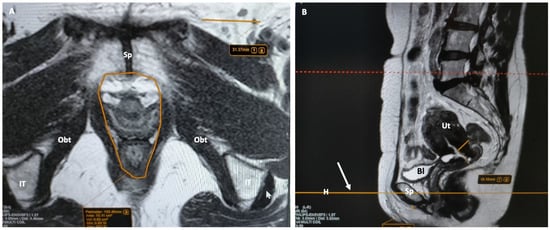

5.1.4. Muscles and Fat Recesses

- Female urethra: This appears as a target-like structure, showing a central hypointense inner ring, which indicates the muscularis mucosa. Surrounding this is a middle, thicker ring of intermediate signal intensity, resulting from a combination of submucosa, longitudinal, and circular smooth muscle. The third, thinner hypointense outer ring represents the striated sphincter muscle. The surrounding space shows high signal intensity, representing connective tissue and smooth muscle within a highly collagenized vascular matrix. Within this space, three distinct ligaments can be identified at specific points along the urethra. At the 30th percentile, the periurethral ligament is visible as a thin hypointense linear structure originating from the medial aspect of the puborectal muscle, running ventrally to the urethra. The paraurethral ligament appears as a slightly oblique hypointense structure connecting the lateral wall of the urethra to the periurethral ligaments (Figure 4). At the 50th percentile, the pubourethral ligament is visible as a hypointense structure connecting the lateral aspect of the urethra to the arcus tendineus fasciae pelvis. In young males, corresponding structures may occasionally be visible in the retropubic space, just anterior to the prostate apex. On sagittal T2-weighted MR, the urethra appears as a cylindrical structure extending from the bladder neck to the external meatus. The signal intensity mirrors that described above, with the internal meatus as the zero point and the external meatus at the 100th percentile.